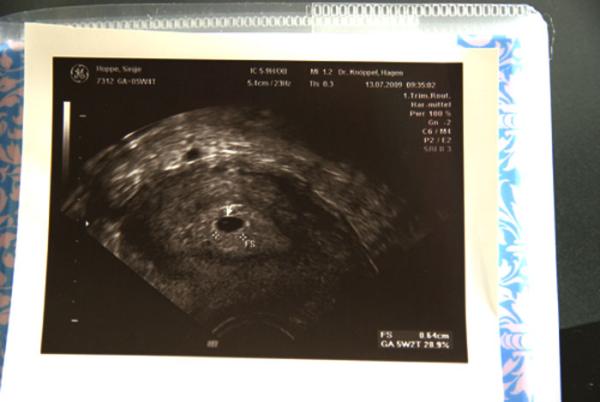

krümel ist 7,9mm groß

Bild zu